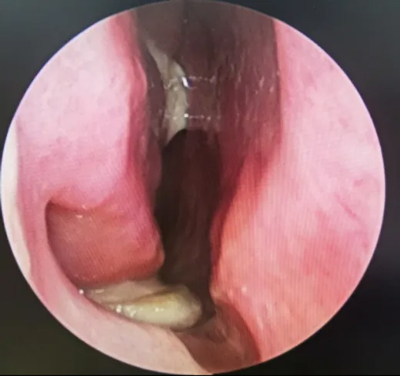

胡少爭主任為他進(jìn)行了

細(xì)致的鼻內(nèi)窺鏡檢查

經(jīng)過

胡少爭主任耐心溝通

高大哥住院并接受了

鼻內(nèi)窺鏡手術(shù)

這是一種微創(chuàng)手術(shù)

術(shù)中將病灶

清理得干干凈凈